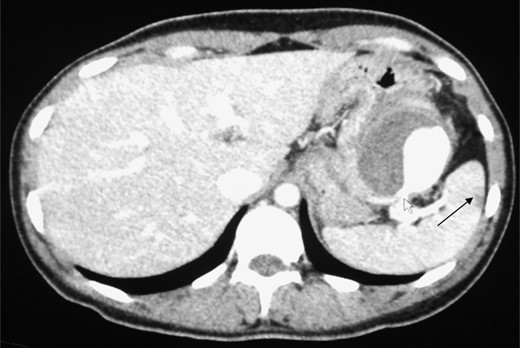

A triphasic, contrast enhanced computed tomography (CT) scan revealed a 6 cm × 5.2 cm well defined, heterogeneous, hypodense mass arising from the pancreatic tail, with an extremely enhancing component (200 Hounsfield units) on its lateral side, a feeder vessel arising from the splenic artery and a small splenic infarct (Fig. 1). Fascial margins of the mass were poorly defined from the splenic hilum and splenic flexure of the large intestine (Fig. 2). CT imaging was supportive of a differential diagnosis of a solid pseudopapillary tumor of the tail of the pancreas with invasion of the colonic wall and compression of the stomach.

CT image showing the ‘ying yang’ sign of the SAA. White arrow shows the origin from the splenic artery. Black arrow shows a splenic infarct.